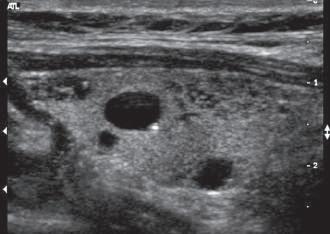

Strain elastography involves measurement of longitudinal tissue displacement before and after compression, usually by manual manipulation of the ultrasound transducer (see Fig. 1.22A). Speckle tracking using radiofrequency backscatter or Doppler is then used to evaluate tissue motion. Strain elastography cannot determine the Young modulus because the compression pressure (stress) cannot be measured directly. Instead, strain ratios are estimated by comparing lesion strain to surrounding normal tissues and displayed in the image in different shades of gray or through color maps (Fig. 1.23). Strain elastography provides an indication of relative stiffness of an area of interest compared to its surroundings.

1.23 Strain Elastograms. The upper frames (A) show in vivo images of swine liver containing a lesion produced by the injection of a small volume of absolute ethanol. In the precompression image (left) the lesion located within the circle is invisible. The elastogram (right) clearly delineates the lesion as an area of increased stiffness compared to the surrounding tissue. The lower frames (B) show a gray-scale image (left) and strain elastogram (right) of a mixed solid and cystic thyroid nodule. In the elastogram the color map displays relative stiffness with softer areas appearing as shades of red, orange, and yellow, and stiffer areas as dark blue. The nodule is heterogeneous with the relatively noncompressible cystic portions differentiated from more compressible surrounding tissue. (Courtesy of P. O’Kane, Thomas Jefferson University.)